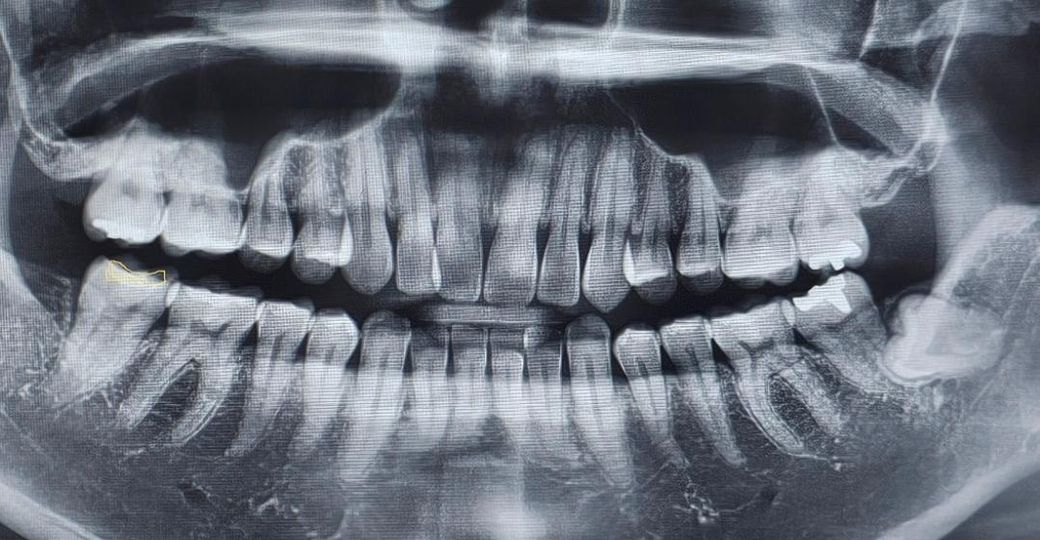

매복사랑니 예방차원에서 발치 필요할까요?

안녕하세요. 기존에 있던 사랑니 2개 제거 후 왼쪽 어금니 옆 매복사랑니 하나 남아있습니다.

사랑니 발치 때 치과에서 매복사랑니는 그냥둬도 된다고하셨는데, 이게 오래 되면 나중에 더 큰 문제가 된다는 글을 봐서요.(치아뿌리흡수되서 제거가 어려워진다 / 염증발생시 옆 어금니도 발치해야된다)

지금은 문제가 없는데 예방차원에서 미리 제거하는게 좋을지 의견 들어보고 싶습니다.

• 1번 째 사진

예방적으로 빼줘야 하는 경우는 옆 어금니와 인접하여 옆 어금니의 치아 뿌리 흡수, 충치 유발 가능성이 있을때 입니다.

지금 엑스레이상으론 근접해보이긴 하는데 정확한 건 ct를 찍어봐야 합니다.